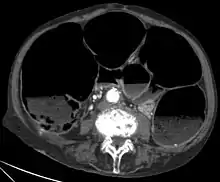

- X-rays – may show intestinal air fluid levels (seen with true mechanical intestinal obstruction)CT-Scan showing a Cross-section of the abdomen of an elderly lady with an IPO.

- CT scans